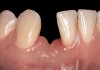

Problem: The implant has bone loss due to peri-implantitis but is not in the esthetic zone and the restoration in place is clinically acceptable. The bone loss has been progressive, and the remaining periodontium is reduced in an area such as a posterior implant (Figure 15 and Figure 16).

Clinical examination showed 2 mm of buccal recession with a shallow vestibule and absence of keratinized attached gingiva against the crown with 8 mm of circumferential pocketing accompanied by bleeding upon probing (Figure 15 and Figure 16). A periapical radiograph showed a symmetrical vertical osseous defect causing the loss of 50% of the bone around the implant (Figure 17). Because the patient had made a significant investment of time and finances to replace her lost tooth with the implant, she desired that the implant and restoration be retained, if feasible.

Fig 15. The implant-supported restoration of tooth No. 19 presented with a lack of attached keratinized gingiva, shallow buccal vestibule, and 2 mm of buccal recession.

Fig 16. The restoration exhibited an 8-mm pocket upon probing, with bleeding on the buccal aspect.